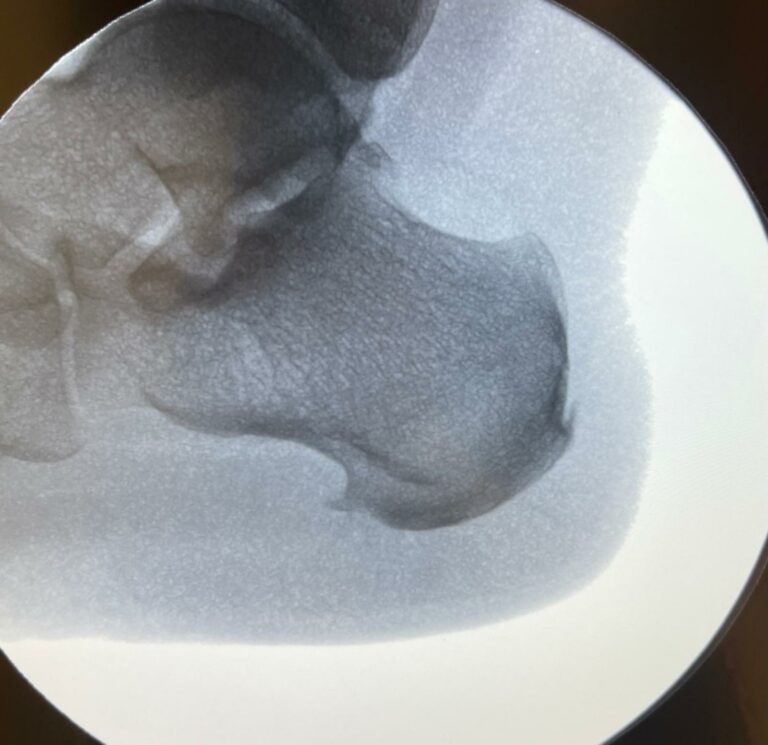

El espolón calcáneo es una calcificación ósea en la parte inferior del talón que puede causar un dolor punzante. Esta afección suele estar relacionada con la fascitis plantar, una inflamación del tejido que conecta el talón con los dedos del pie.

En Clínica Arriaga, realizamos la cirugía de espolón calcáneo mediante la técnica MIS, un procedimiento ambulatorio con mínima invasión que elimina la calcificación ósea de manera precisa.

El tratamiento se realiza bajo anestesia local y sin necesidad de hospitalización, permitiendo al paciente regresar a su domicilio el mismo día. Gracias a este método, la recuperación es más rápida y con menos molestias en comparación con técnicas tradicionales.